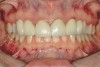

Figure 2a  Corticotomy SFOT. The patient presented with unesthetic anterior bridgework that was placed at age 14 to compensate for congenitally missing Nos. 7 and 10.

Figure 2a

Figure 2b  A corticotomy in SFOT is a surgical technique in which only the cortical bone is cut, perforated, or mechanically altered to the depth of the medullary bone and the medullary bone remains intact.

Figure 2b

Figure 2c  One week postsurgery with mesial buildups on Nos. 5 and 12 and thin pontics on archwire to conceal spaces during closure.

Figure 2c

Figure 2d  Prerestorative orthodontics was completed in 5 months. Final result 3 years, 4 months after completion.

Figure 2d

Figure 2e  Teeth Nos. 5 and 12 were converted to Nos. 6 and 11, and Nos. 6 and 11 were converted to Nos. 7 and 10. Nos. 4 and 13 were enlarged. Note stability and absence of orthodontic relapse. Before-and-after smiles.

Figure 2e

Figure 2f  Teeth Nos. 5 and 12 were converted to Nos. 6 and 11, and Nos. 6 and 11 were converted to Nos. 7 and 10. Nos. 4 and 13 were enlarged. Note stability and absence of orthodontic relapse. Before-and-after smiles.

Figure 2f

Figure 2g  Periodontist: Edward P. Allen, DDS, PhD. Prosthodontist: Robert R. Winter, DDS.

Figure 2g

Figure 2h  Periodontist: Edward P. Allen, DDS, PhD. Prosthodontist: Robert R. Winter, DDS.

Figure 2h